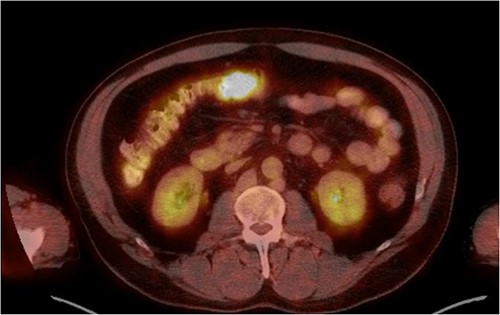

He was then referred to gastroenterology and underwent diagnostic colonoscopy that showed a large polypoid mass in the transverse colon that was partially obstructing. Gastroenterology then obtained a CT scan of the chest, abdomen and pelvis that showed wall thickening of the colon (Figs 1–3). Ultimately when pathology confirmed malignant melanoma, a PET scan was ordered that showed increased uptake at the previously seen and biopsied transverse colon mass (Fig. 4).

Axial CT scan with IV contrast showing thickened transverse colon.